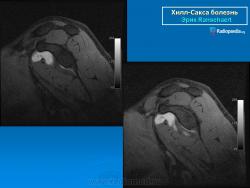

На рентгенограмме плечевого сустава определяется умеренный остеопороз головки плечевой кости. Иногда на ее задненаружной поверхности позади вершины большого бугорка выявляется вдавленный дефект (повреждение Хилл-Сакса). Дефект четко виден на рентгенограмме в аксиальной проекции. Аналогичный, но менее выраженный дефект может быть выявлен в зоне передненаружного края суставной впадины лопатки. Также в диагностике причин привычного вывиха плеча помогает МРТ исследование.